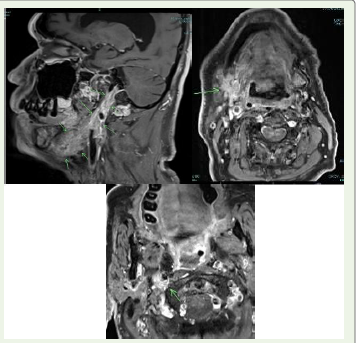

Case Presentation:A 75-year-old man presented with two months of progressive dysphagia, muscular twitching of the tongue, and weakness. Neurophysiology confirmed motor neuronopathy. PET CT revealed a carotid bifurcation mass and hypermetabolic rectosigmoid thickening. Biopsy of a cervical lymph node demonstrated moderately differentiated adenocarcinoma. Intravenous corticosteroids resulted in only partial improvement, but subsequent targeted radiotherapy to the primary malignancy led to marked and sustained recovery of bulbar and motor function.

Investigation findings are outlined in [Table 1].Clinical course:

Given high aspiration risk, an NG tube was inserted. He was

deficits persisted.Following confirmation of adenocarcinoma, the patient underwent targeted radiotherapy to the suspected rectosigmoid primary and regional nodes. In the weeks after radiotherapy, his bulbar function, swallowing, and gait improved significantly, and he was able to resume partial oral feeding. This dual pattern suggested an immune-mediated, paraneoplastic motor neuronopathy, partially steroid-responsive but substantially improved only after oncologic treatment.

Several features in this case strongly favored a paraneoplastic motor neuronopathy over classical ALS. The temporal profile was subacute, progressing over weeks rather than months to years. Neurological findings were predominantly lower motor neuron in distribution, without upper motor neuron signs, and remained nonprogressive over 12 months of follow-up. Anti-Hu antibody positivity provided serological evidence of a high-risk paraneoplastic antibody associated with malignancy-related neurological syndromes. There was a clear temporal association between neurological onset and the diagnosis of metastatic adenocarcinoma. Most importantly, the patient demonstrated partial responsiveness to corticosteroids and marked, sustained improvement following definitive tumor directed radiotherapy, an outcome incompatible with the natural history of classical ALS.

two features, that is the presence of a carotid bifurcation lesion and

an LMN facial palsy, could suggest direct tumor infiltration of cranial

nerves. Local compressive or infiltrative effects remain an important

differential diagnosis in patients with focal adenopathy.Paraneoplastic etiology remains more likely in our case rather than an isolated local invasion due to the following several points: